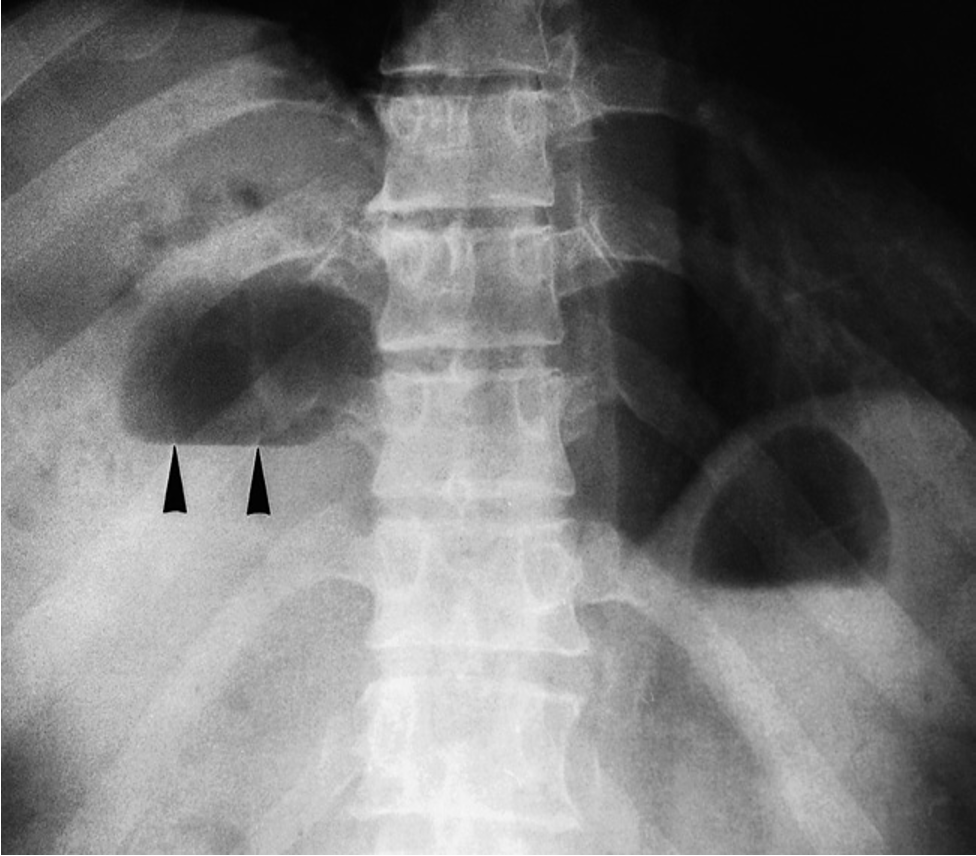

Gas in a right subphrenic abscess. There are several collections of gas within the abscess. The largest of these contains a fluid level (arrowheads). The air–fluid level under the left hemidiaphragm is normal. It is in the stomach.